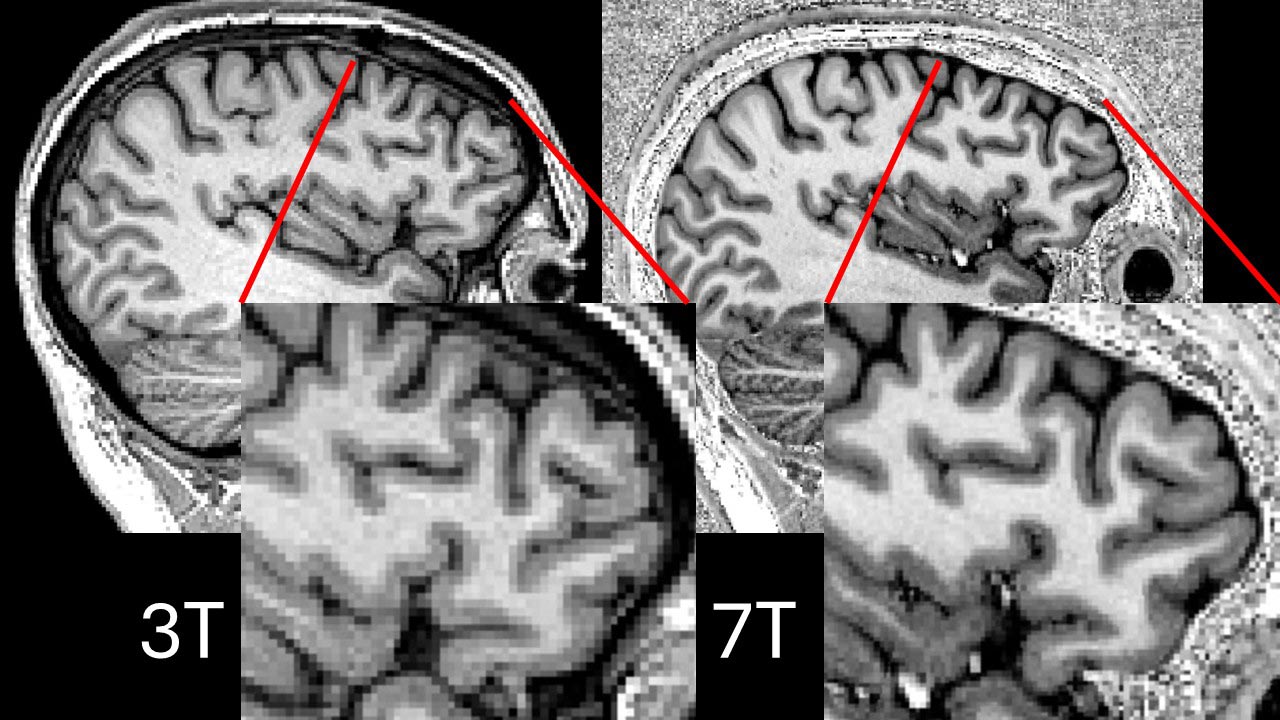

Ultra-high field 7T MRI scanners allow much more detailed resolution on brain scans and have been shown in other countries to be better than the NHS’s best 3T MRI scanners at detecting these lesions in patients with drug-resistant epilepsy (and in fact, most NHS hospitals have even weaker, 1.5T scanners). However, 7T MRI scans are susceptible to dark patches known as signal dropouts. These dropouts commonly occur in the temporal lobes, where most cases of epilepsy arise.

Parallel transmit 7T images were clearer than conventional (‘single transmit’) 7T images in more than half of the cases (57%), and in the remaining cases the images were equally clear. Single transmit scanners never outperformed parallel transmit scanners.